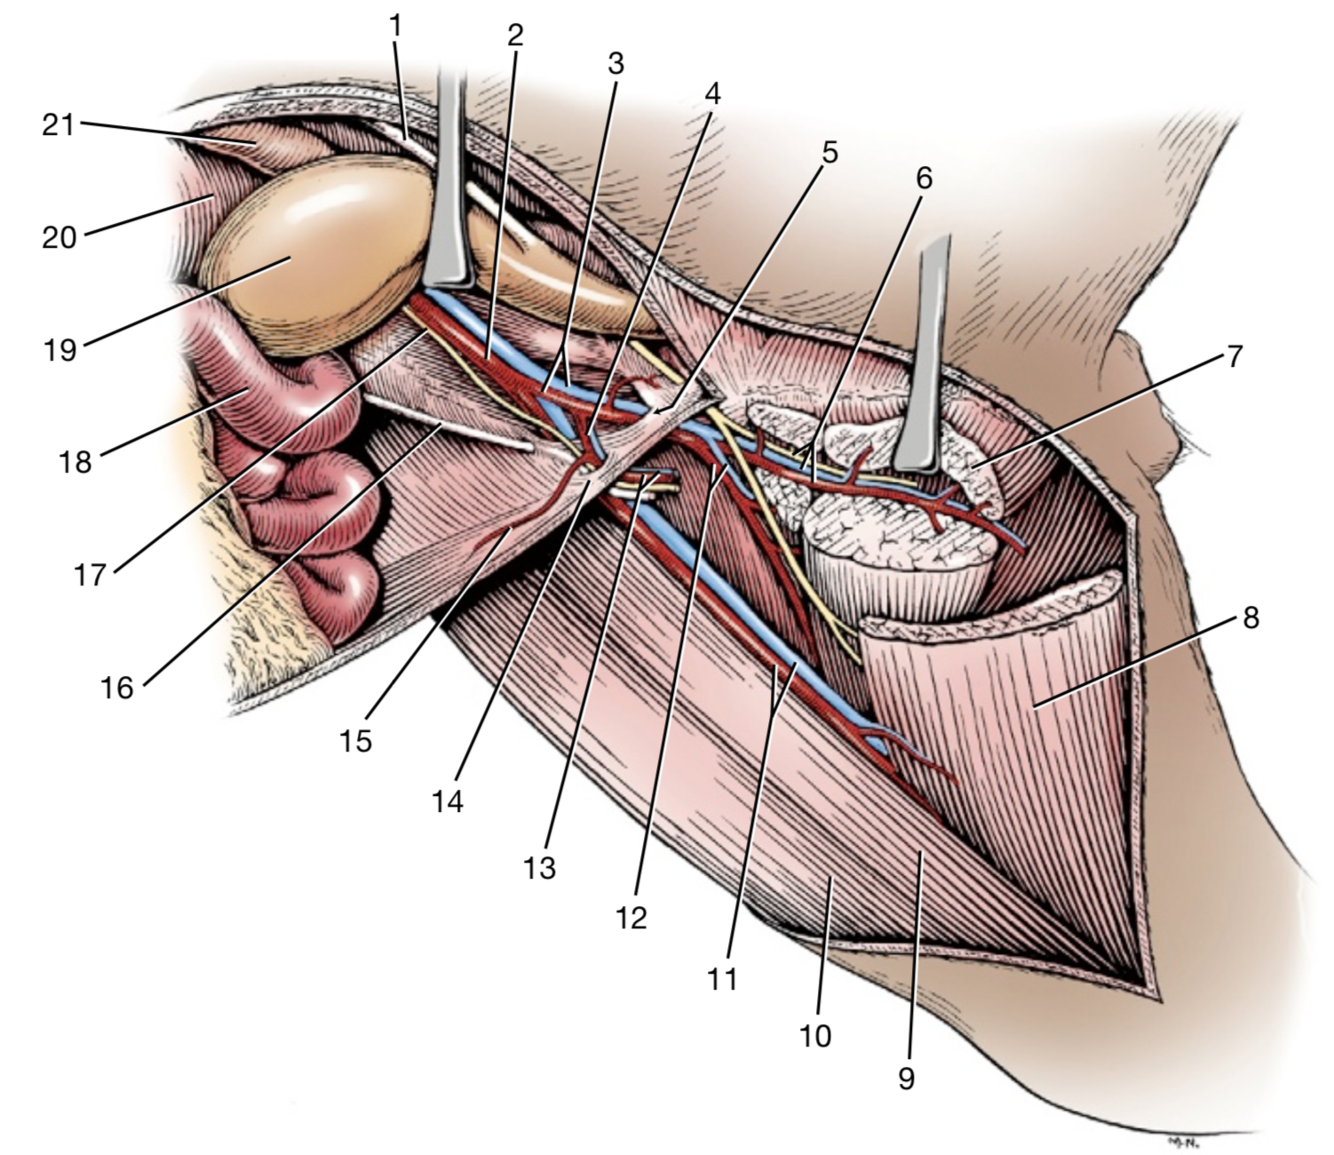

1

Crus mediale

2

Crus laterale

A./v. pudenda externa

A./v. femoralis

Processus vaginalis

A./v. pudenda externa